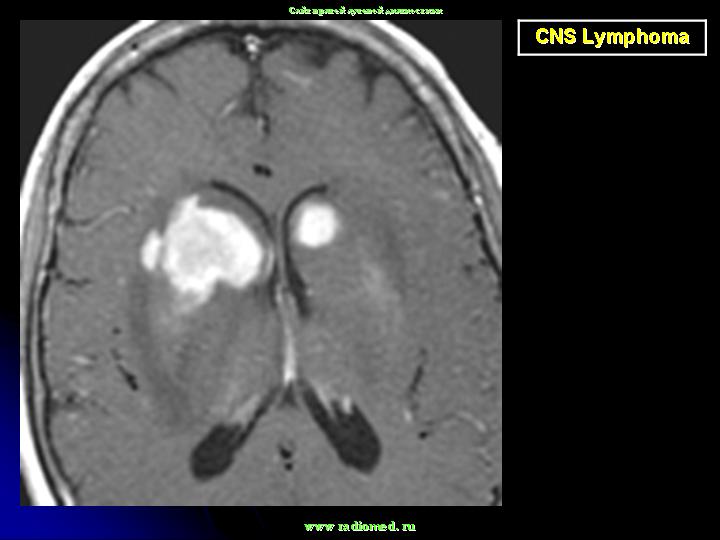

Локализируется в основном в больших полушариях. Некоторые больные могут иметь лимфому в других частях тела. В головном мозгу, не редко, могут иметь место множественные локализации.

Диагноз подозревается на основе изображений КТ и МРТ.